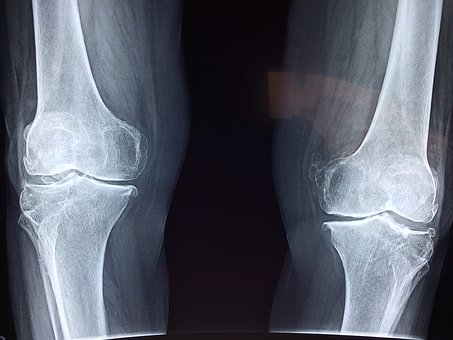

膝の痛み

怪我による膝の痛みに対するプライトン固定で早期改善した症例